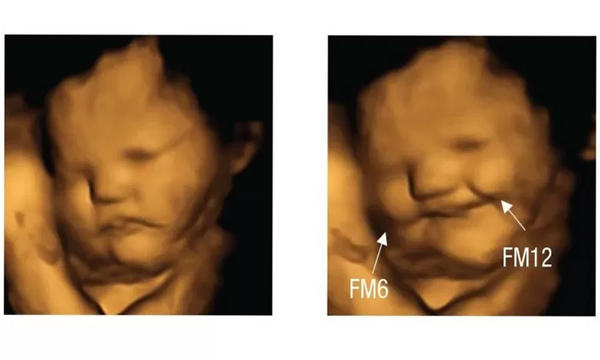

Si el sabor de la col rizada te hace fruncir el ceño, no estás sola. Los científicos han descubierto que los fetos en el útero parecen sonreír después de que sus madres comen zanahorias y fruncen el ceño después de que coman esa col. El Laboratorio de Investigación Fetal y Neonatal de la Universidad de Durham, en Reino Unido, afirma que es la primera evidencia directa que muestra fetos respondiendo a diferentes sabores en tiempo real. Los investigadores estudiaron a unas 100 mujeres embarazadas y a sus bebés por nacer en Inglaterra. Les dieron a 35 mujeres cápsulas que contenían zanahorias en… ...[Leer más]